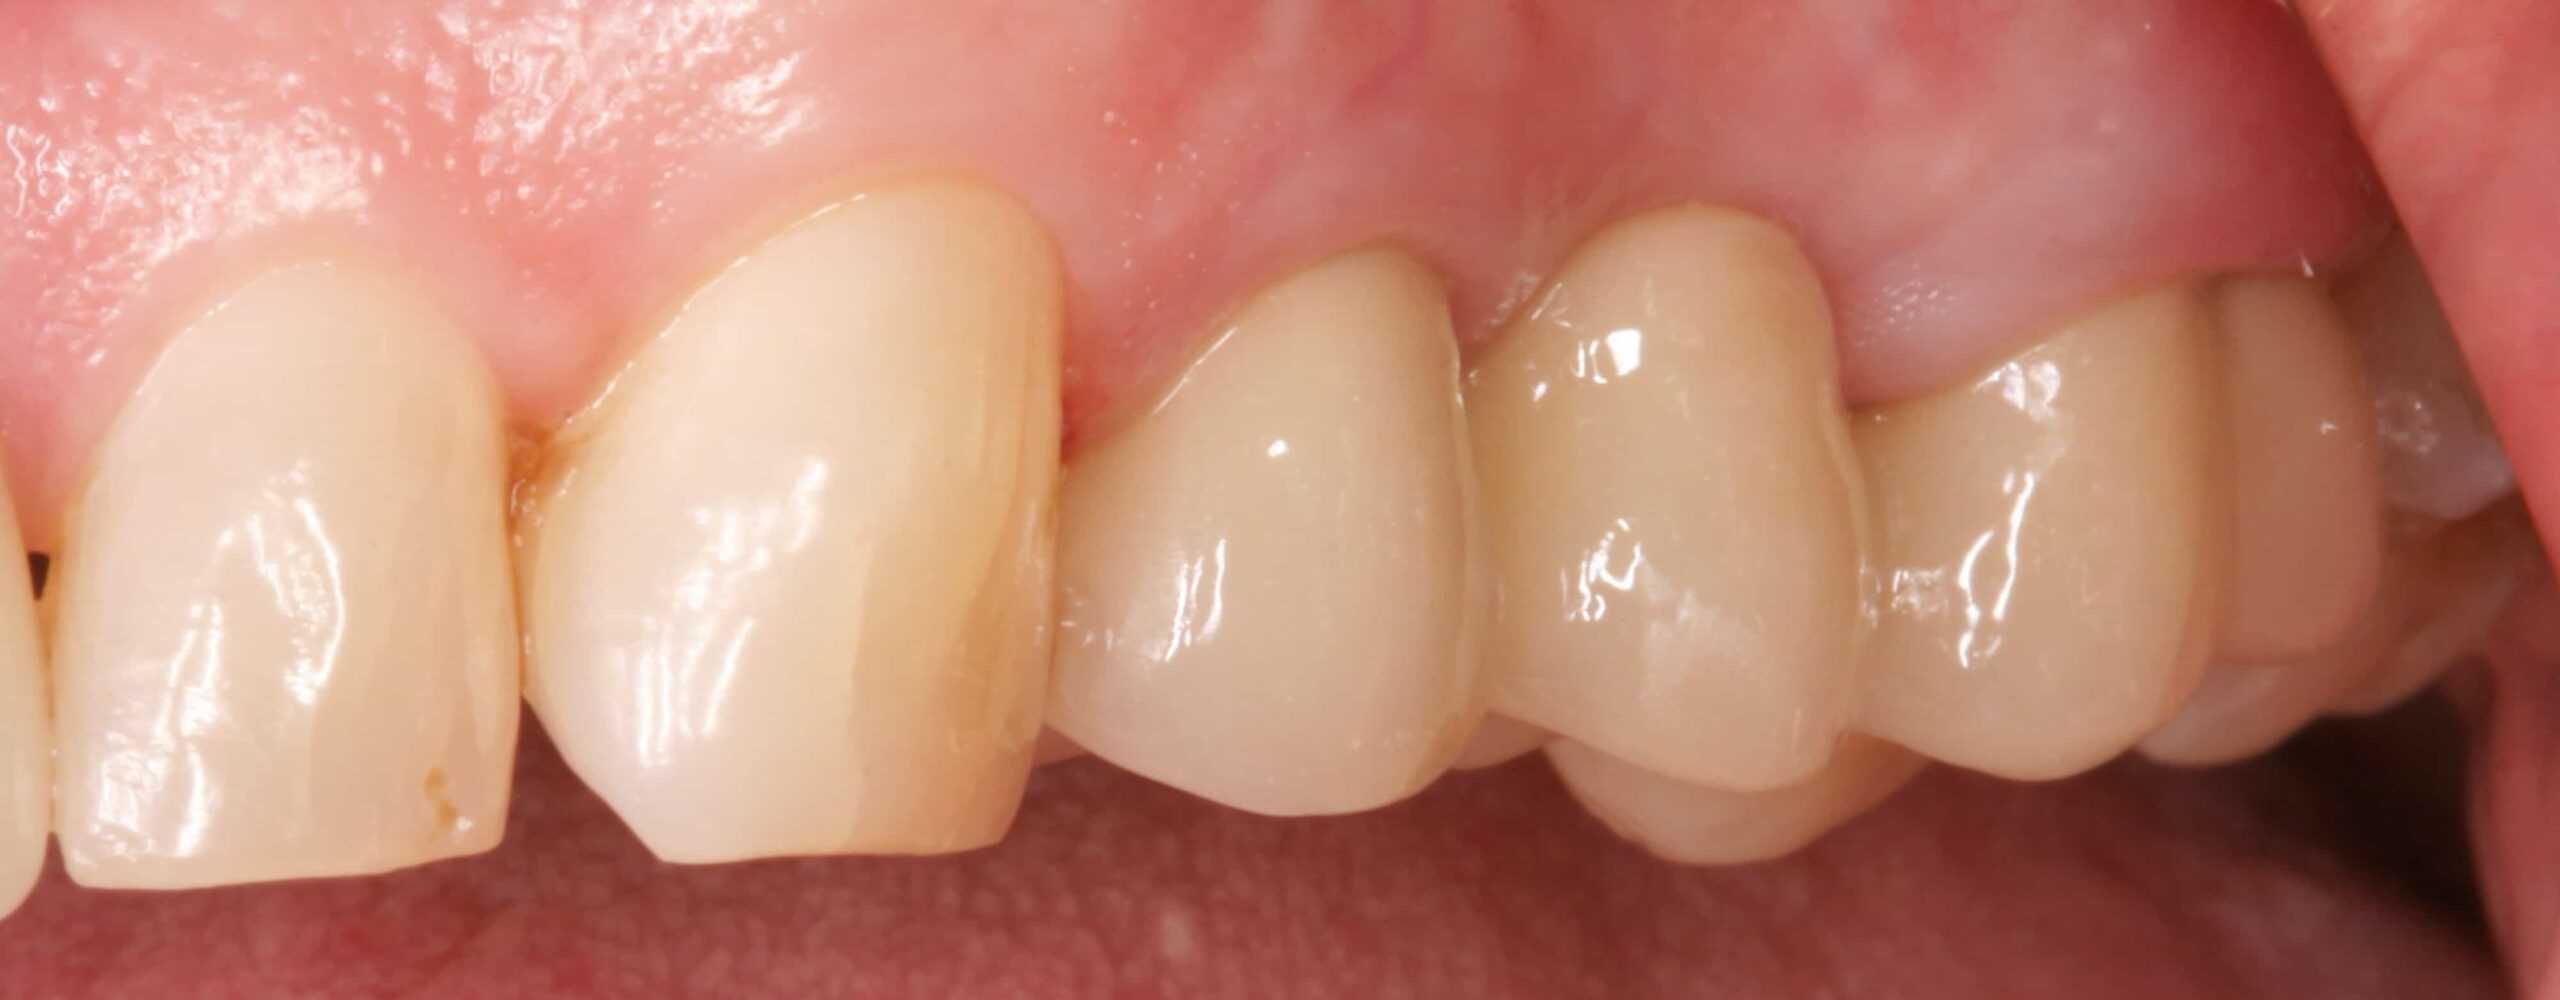

Case Study Details

Posterior; Tooth Supported Bridge (Fixed Partial Denture)

After:Â Revision crown and bridge therapy. Tooth #14 was carious and required root canal therapy and a build-up (foundation restoration) prior to definitive bridge therapy. Three-unit fixed partial denture (bridge), porcelain fused to gold, abutment teeth 12 and 14.